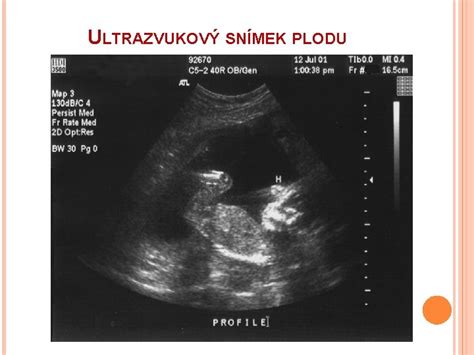

Vyvíjející se miminko se začne pohybovat mnohem dříve, než je jeho maminka schopna to cítit. První pohyby se objevují již v 7. až 8. týdnu těhotenství. Dle ultrazvukového vyšetření lze první pohyby miminka sledovat již v sedmém týdnu těhotenství. První pohyby jsou jen občasné, ale postupně se zlepšuje jejich koordinace v důsledku vývoje a zrání centrálního nervového systému plodu.